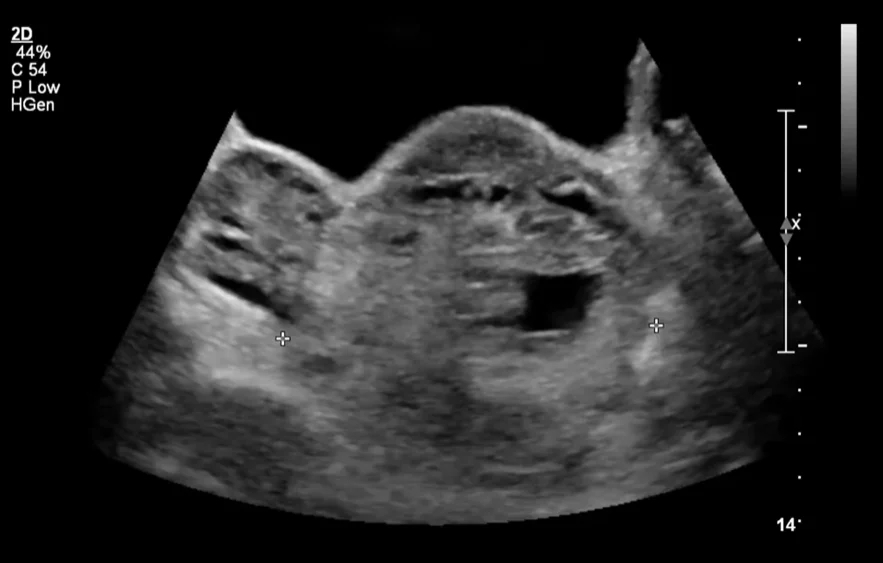

• Xoắn buồng trứng trong thai kỳ (Ovarian Torsion in Pregnancy).

• Khối u phần phụ trong thai kỳ (Adnexal Mass in Pregnancy)